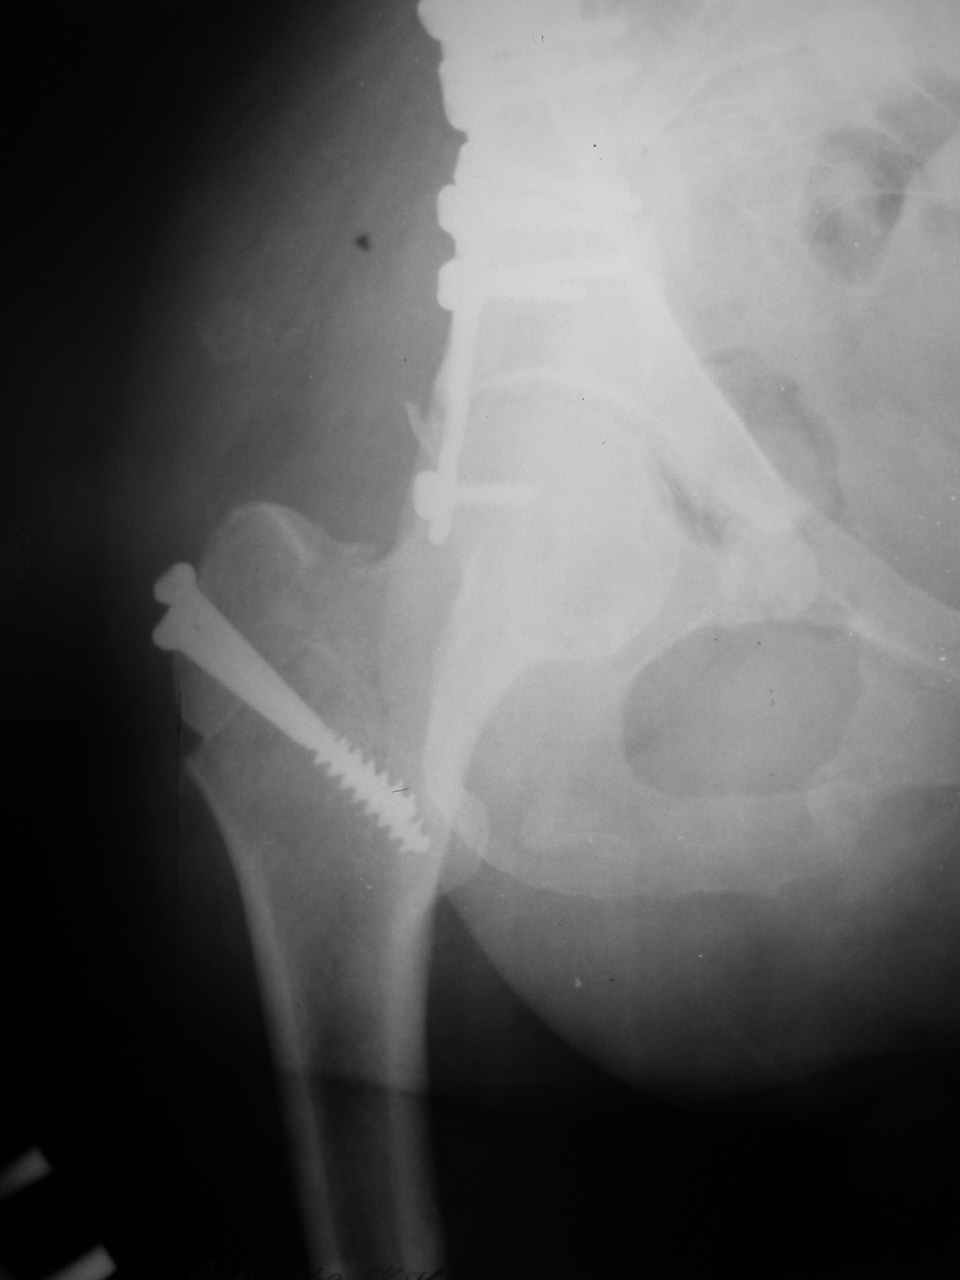

Сложностью, ассоциативностью характера перелома, я бы с радостью воспользовался мининвазивной перкутанной фиксацией винтами, но боюсь, что результат был бы ещё хуже, техникой непрямой репозиции перелома не владею, поэтому пытаясь получить анатомичную впадину приходится широко открывать, по крайней мере пока, а дальше буду пытаться уменьшать пространство...

> передним доступом на двухколонный перелом?

Илеофеморальный доступ не совсем передний и сравнительно с илеоингвинальным, и Кохера-Лангенбека открывает весь наружный таз кроме самых передних отделов лонных костей, фиксацию которых я не ставил в задачу. Обширность диссекции, большая длительность операции и более высокий риск гетерооссификации - отрицательные моменты в обмен на возможность легче ориентироваться.

> должен быть чрезвертельным боковым (как и советовал Рунков) или двумя

> доступами.

Комбинированные доступы - хорошая альтернатива, меньший процент осложнений, но я заметил , что без сбора *мозаики* безымянной кости сложно отрепонировать переднюю колонну, а с нерепонированной передней колонной невозможно анатомично собрать заднюю колонну и соотв. фрагменты стенки - так.что все равно открывать придется широко. Поэтому выбирая комбинированный

подход, передний доступ должен был бы быть продлен до задней трети крыла безымянной кости, а задний - практически до того же уровня, оставляя 6-7 см мостик. При этом вместо одного послеоп. рубца у больного остаются два сравнительно длинных.